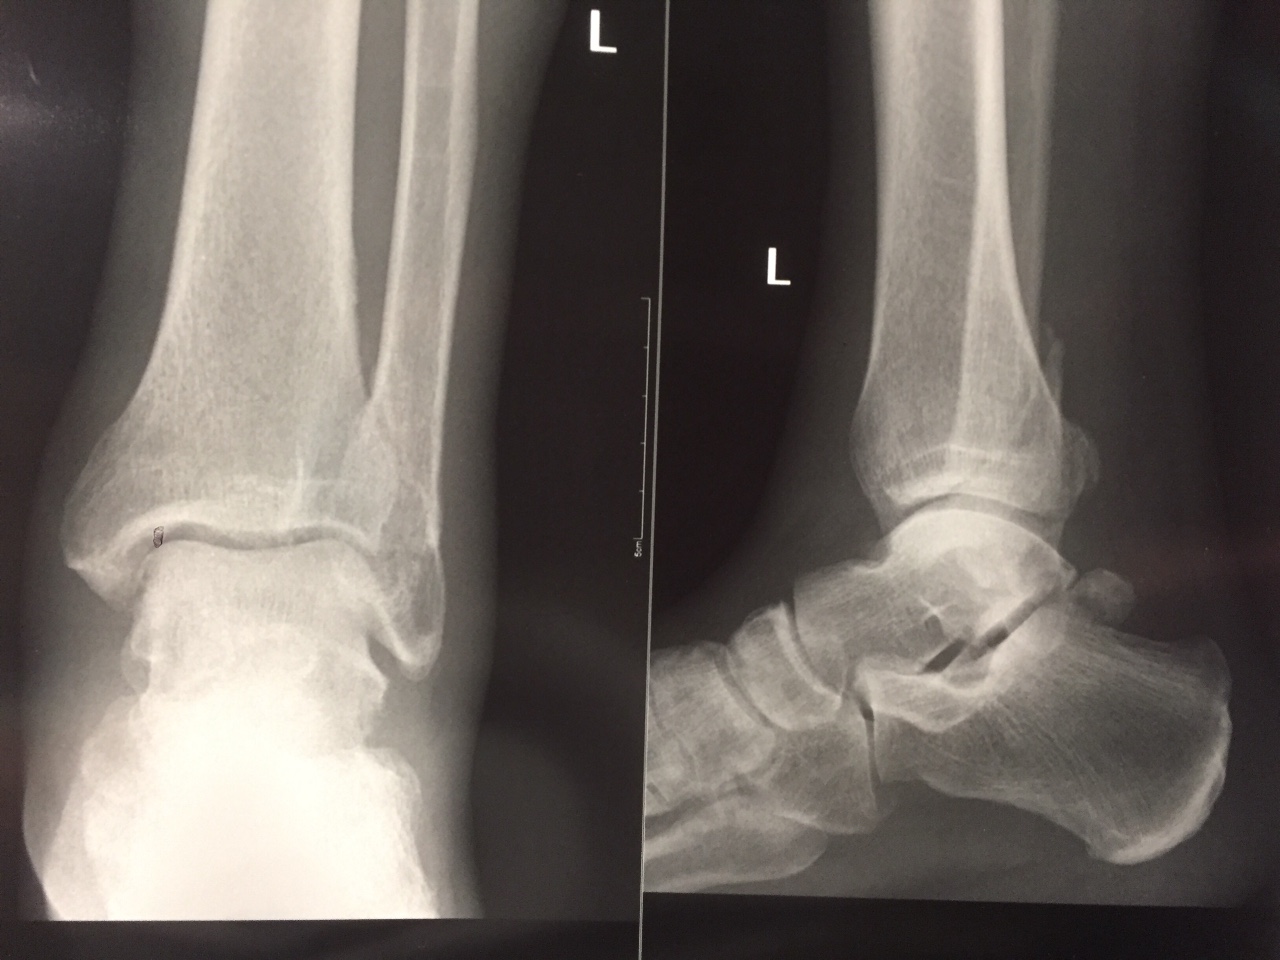

Перелом большой берцовой кости - серьезное повреждение, сопровождающееся болезненными ощущениями и нарушением функции ноги. На этой странице вы найдете много фотографий, позволяющих вам более детально изучить эту травму.

Чрескостный остеосинтез лодыжки

Остеосинтез двухлодыжечного перелома

Здесь представлены медицинские изображения переломов большой берцовой кости, сделанные врачами в процессе диагностики и лечения. Вы сможете увидеть, как выглядит этот тип травмы на рентгеновских снимках и других медицинских изображениях.